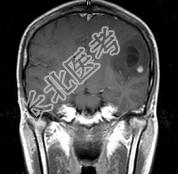

- 单项选择题女,33岁, 三个月前有右上肢及右颜面部麻木,伴耳鸣及头昏, 请根据所提供图像,诊断最有可能是 ( )

A、星形细胞瘤

B、脑血吸虫病

C、脑转移瘤

D、脑结核

E、脑脓肿